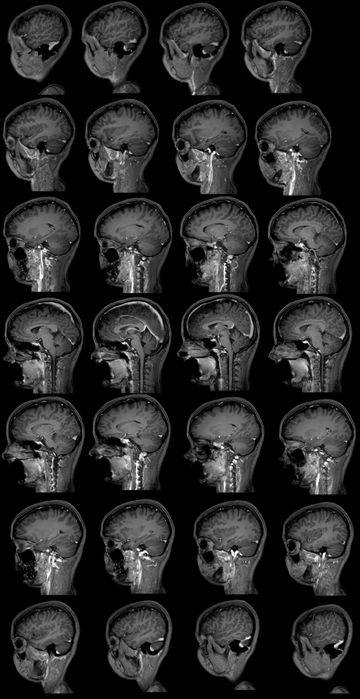

Now at the age of 18, 1 year and a half without medication, she presented another generalized tonic-clonic seizure. One day before, she referred abscence but did not have certainty, the same day she had very little sleep and related absences. After, she had a generalized seizure, that lasted approximately 3 minutes, with tongue bite, no sphincter release and a postictal state of approximately 40 minutes. In the hospital, she had a blood screening that showed normal indices in the hemogram, of potassium (4.7mEq/L) and creatinine (0.8 mg/dL). It was prescribed Sodium Divalproex 250mg 2 times a day (12/12h). After, the Neurologist did a full neurological physcial exam that was completely normal. It was also requested an ECG (Figure 5), with photostimulation and hyperpnea, that had no compatible abnormalities of AS and a contrasted MRI (Figure 6) with no changes. The conduct was taking the medication at the right time, follow up every 6 months and beware if any changes or absences.

Figure 6 Magnetic resonance image scan of the brain.